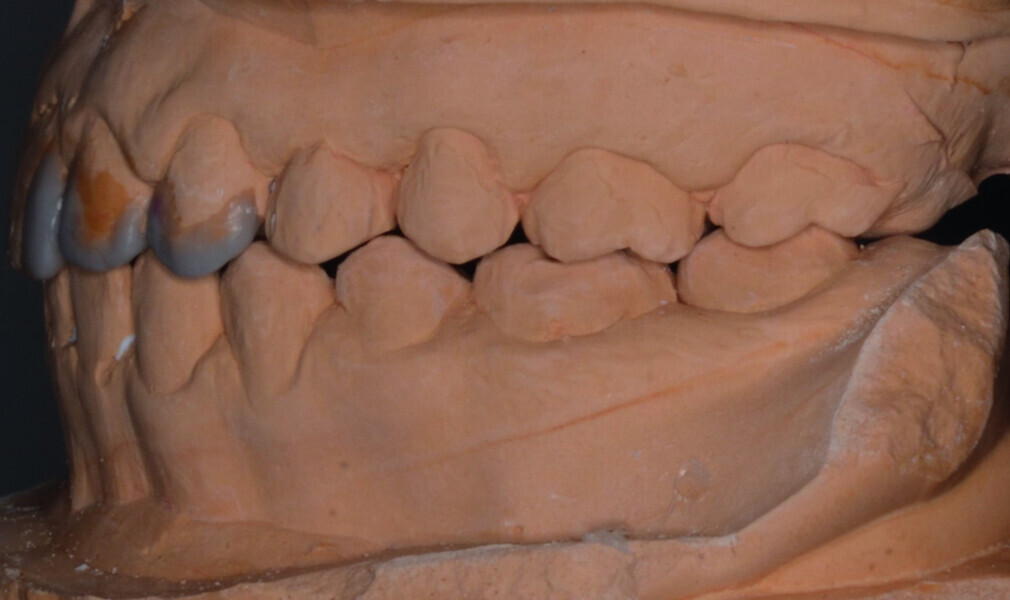

Orthodontic management of maxillary lateral incisors agenesis